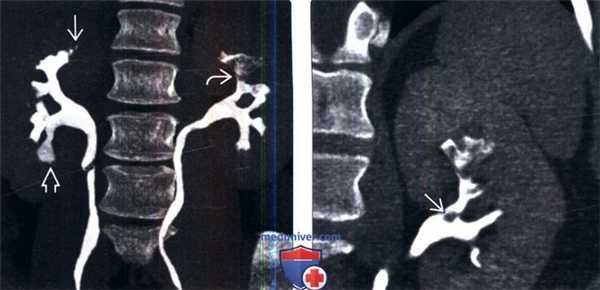

(Слева) На рисунке показано ишемическое поражение нескольких почечных пирамид В с отторжением некоторых сосочков В, один из которых лежит свободно в собирательной системе.

(Справа) КТ-урография с контрастированием, коронарная проекция: у мужчины 33 лет с внутривенным употреблением наркотиков в анамнезе выявлены отсутствие нормальных пирамид верхнего полюса правой почки, притупленные закругленные чашечки. Сравните их с чашечками нормальной формы слева и пирамидами на фоне затемненных контрастом канальцев.

(Слева) КТ-урография, коронарная проекция: у женщины 46 лет с серповидноклеточной анемией выявлены булавовидные чашечки, скопление контрастного вещества в месте некротизированных сосочков и аморфные органические остатки в чашечках верхнего полюса левой почки. Это классические признаки, указывающие на папиллярный некроз.

(Справа) КТ с контрастированием в проекции максимальной интенсивности, коронарная проекция: у того же пациента обнаружен один некротизированный сосочек В с аморфными органическими остатками в собирательной системе.